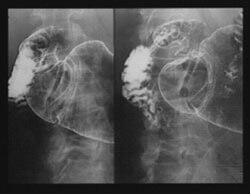

Dans un essai clinique en double aveugle portant sur 38 patients, des chercheurs ont constaté qu'une dose orale de 1 g de mastic par jour pendant une période de deux semaines entraînait un soulagement des symptômes dans 80 % des cas chez des patients avec un ulcère duodénal traité avec le mastic contre 50 % dans le groupe témoin. L'étude a également apporté des preuves endoscopiques que le mastic favorisait la guérison des tissus de la muqueuse gastrique. Les ulcères ont été complètement remplacés par des cellules épithéliales saines12. La guérison de l'ulcère a été complète chez 70 % des patients prenant le mastic contre 22 % dans le groupe placebo. |

| Élimination d'H. pylori

Des chercheurs ont rapporté que le mastic était un agent antibactérien efficace dans le traitement de Helicobacter pylori. Dans leur rapport, ils ont noté que même de faibles doses de gomme de mastic - 1 g par jour pendant deux semaines - pouvaient traiter les ulcères peptiques très rapidement. Ils ont constaté que le mastic agissait contre Helicobacter pylori, ce qui pourrait expliquer ses effets thérapeutiques chez des patients atteints d'ulcères peptiques13. |

Des chercheurs ont réalisé des tests in vitro qui ont révélé que le mastic tuait efficacement 99,9 % d'H. pylori lorsqu'il était testé contre différentes souches - NTCC 11637 (une souche de référence standard) et six isolats cliniques en incluant trois résistantes au métronidazole. |

Il faut souligner que le mastic était également efficace contre les souches d'H. pylori résistantes au médicament, même à très faibles concentrations. Ces résultats suggèrent que le mastic a des activités antibactériennes très nettes contre H. pylori. Ces activités pourraient au moins en partie expliquer les propriétés anti-ulcéreuses du mastic. |